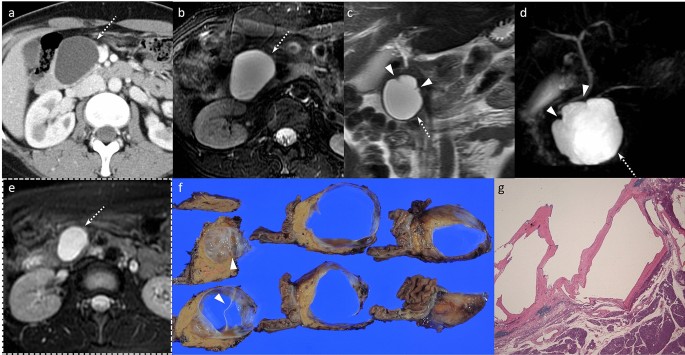

MRI revealed a septated pancreatic head cyst of 7 cm with a smooth capsule without lobulation and no connection to the pancreatic duct Surgery showed a low grade mucinous cystadenoma with ovarian stroma Mucinous cystadenoma CT images of a 30 year old female with a history of a biliary pancreatitis and cholecystectomy She had sudden increased left abdominal pain USEndoscopic ultrasound with fine needle aspiration is useful in pancreatic cysts smaller than 3 cm BMC Gastroenterol Dec 9; (1)413 doi /s Some doctors will elect to observe small pancreatic cysts (smaller than 2 cm) without malignant characteristics every six to 12 months with scans They will consider studying larger pancreatic cysts (more than 2 cm) and enlarging cysts with endoscopic ultrasound and at the same time may insert a needle into the cyst to obtain cyst fluid

67%) and/or a thick cyst wall (2 of 6 cysts;Loss and no jaundice is found to have a 3 cm cyst in the pancreatic body by CT scan performed due to abdominal pain Slight stranding of the pancreas adjacent to the cyst is noted but otherwise the pancreas and ductal system is normal No connection to the pancreatic duct is noted Serum lipase is normal 40 41 42The site of origin of congenital pancreatic cysts is variable and the majority is localized in the tail or neck of the pancreas (62%), whereas localization in the head of the pancreas was reported in 32% of cases In both of our patients, the cysts were related to the head and body of the pancreas Congenital pancreatic cysts originating in the neck and tail of the pancreas are often confused

For many patients, a pancreatic cyst — which may not be a true cyst but a pseudocyst that lacks the specialized cells that secrete fluid into the space they occupy — will go away without treatment Many doctors prefer to use a method called watchful waiting, where no treatment is given and the cyst is monitored for changes Often, a benign cyst will resolve within six weeks and no Serous cystadenomas are benign focal cystic lesions which usually include multiple, small (12 cm in diameter) cysts separated by thick fibrous septa, resembling a honeycomb (Fig 4) They can be located anywhere in the pancreas and are rarely malignant, opposite to IPMNs and mucinous cysts Lymphoepithelial cysts are very rare cystic lesions of the pancreas They usually measure less than 5 cm and are seen in men The cysts are lined by squamous epithelium and surrounded by dense lymphoid tissue Their imaging appearances vary and they may be either unilocular or multilocular

Please use the navigation on the left to access information about these different types Cystic neoplasms of the pancreas include serousGross examination of the resection specimen revealed a 09 cm unilocular cyst The lining of the cyst was smooth Serial cut sections of the specimen revealed the cyst to be near the duodenum and adjacent to the common bile duct Figure 1) Figure 1 a Gross appearance of the specimen b Retroperitoneal margins inked with three different colors c Sections of the pancreas showing a A pseudocyst is usually rich in pancreatic enzymes and is usually sterile Pseudocysts are mostly single but can be multiple in 10% of cases They are commonly round or oval, but some may be multilocular and irregular in shape (Figure 1) The size of pseudocysts varies from 2 to cm (68)